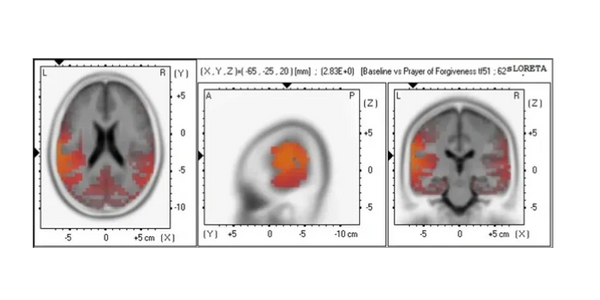

The main effect between the two conditions, Baseline (Not Praying) vs Prayer of Forgiveness was significant t(44) = 2.83, p = .003494, suggesting that when Christians focused on asking God for forgiveness of sin, there was elevated alpha current source density (alpha CSD t-max voxel value (2.83E+0) in the left postcentral gyrus (BA 40) brain region. SnPM imaging results are presented.